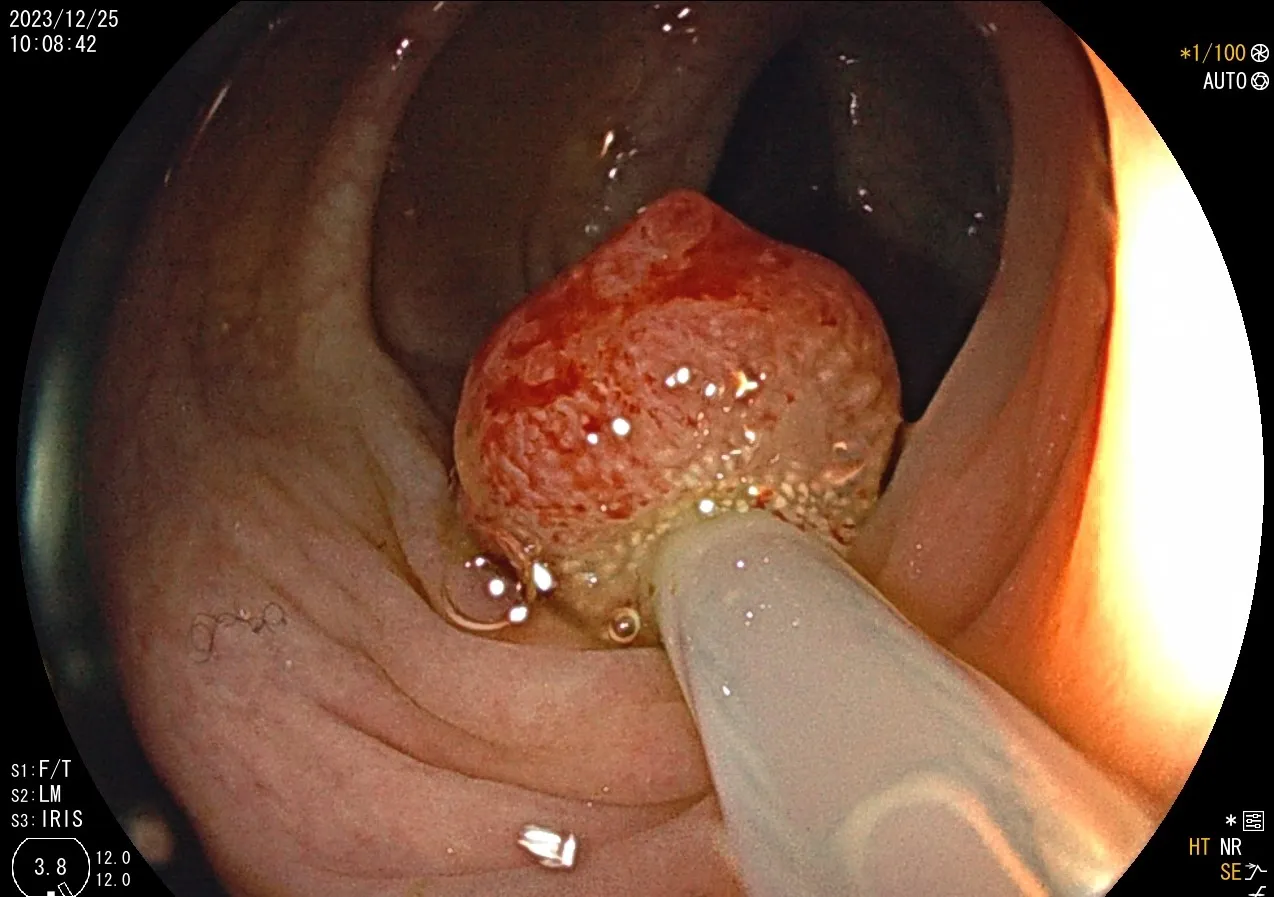

年前,一位40歲無任何病史的吳小姐來院接受全套健檢,於無痛大腸鏡的檢查中,在乙狀結腸意外發現一顆約1.5公分的息肉,當下使用BLI 觀察息肉型態,認為是NICE分類第二型(腺瘤),當下執行息肉切除術將整顆息肉完整切下並送化驗,結果病理報告診斷為大腸癌;